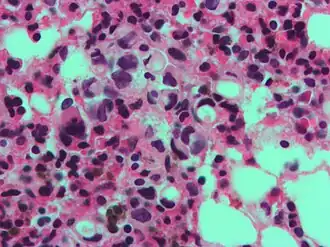

Een zegelringachtige opgeblazen macrofaag, die een kankercel kan nabootsen, maar de textuur van de kern is vergelijkbaar met die van een normale macrofaag.